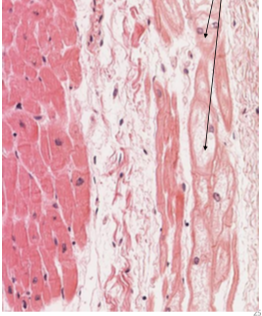

What is indicated by the arrows

Purkinje fibers

Purkinje Fiber

Involuntary innervation by autonomic nervous system

Pacemaker system of modified cardiac muscle cells that generate and coordinate myocardial contractions during cardiac cycle (Purkinje system)